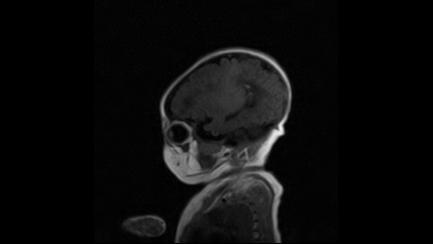

标题: PED3413:患儿女6天体检

缺血缺氧性脑病

6天为新生儿,髓鞘发育正常;左侧颞顶叶蛛网膜下腔增宽,请结合临床。

1。缺血缺氧性脑病2。左侧颞顶叶外部性脑积水,可观察

半卵圆中心上方层上可见对和乐大脑皮质t1高信号,考虑有hie可能,不知有何症状,建议加做dwi及复查

符合缺氧缺血性脑病影像表现。